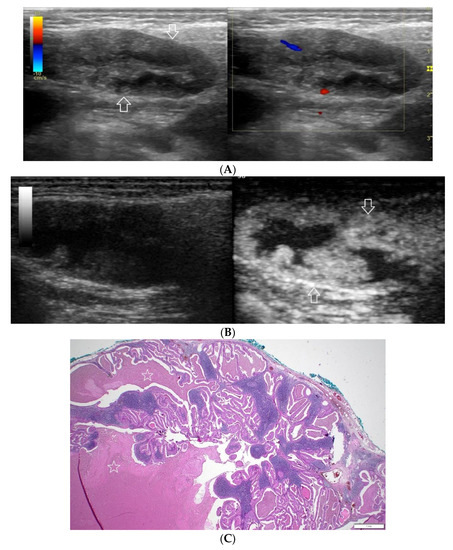

Figure 5.

(A−C) Warthin’s tumour. (A) Routine ultrasonographic examination in B presentation and colour Doppler: a small multi-arched hypoechogenic, well-demarcated focal lesion of a heterogeneous echostructure. On CD, low blood flow is observed. (B) Contrast-enhanced imaging in arterial phase: a strong homogeneous enhancement of a peripheral part of the lesion (white arrows). A weakly enhanced central part. (C) Pathomorphological image, H & E stain. Large areas of irregular shape containing fluid (white stars). A part containing glandular tissue located peripherally. Black star indicates a lymph node.